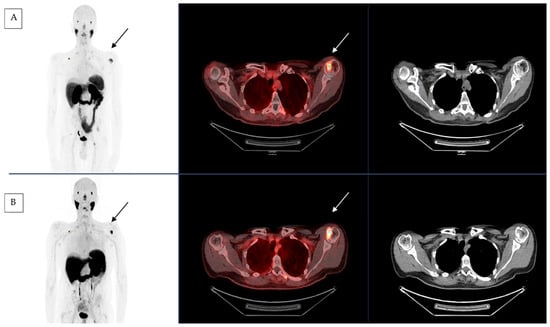

2.2. [177Lu]Lu-PSMA-617 Therapy Used in Salivary Gland Cancer

2.3. First Compassionate Use of [177Lu]Lu-PSMA-617 in Salivary Gland Cancer in France